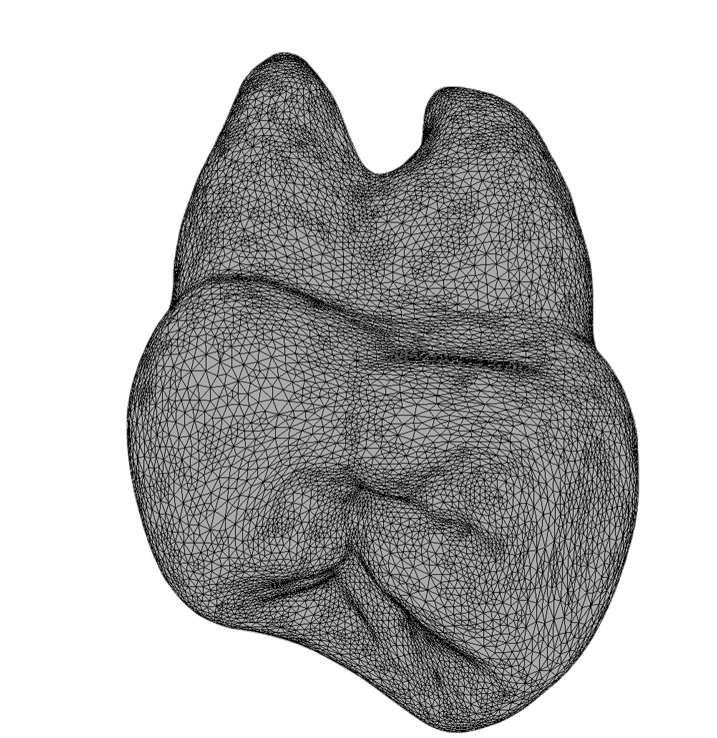

(7.) A 3D image of the mesial aspect of a maxillary first molar with the challenging concave region leading to the furcation shaded.

Figure 7